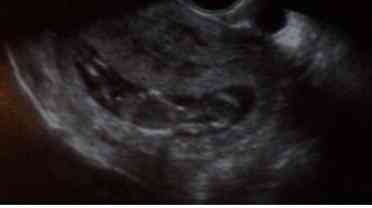

♥ 28.1.2008 - poradna proběhla v pohodě, vycucli nám 6 zkumavek krve na všechno možné včetně tripple testů a udělali 1.utz přes bříško. Mimísek se krásně vrtěl 🙂 a podle hlavičky odpovídá 16+4, podle nožiček 16+2. A od hlavičky po kostrč měří 11,4cm 🙂. Zůstáváme ještě na neschopence.